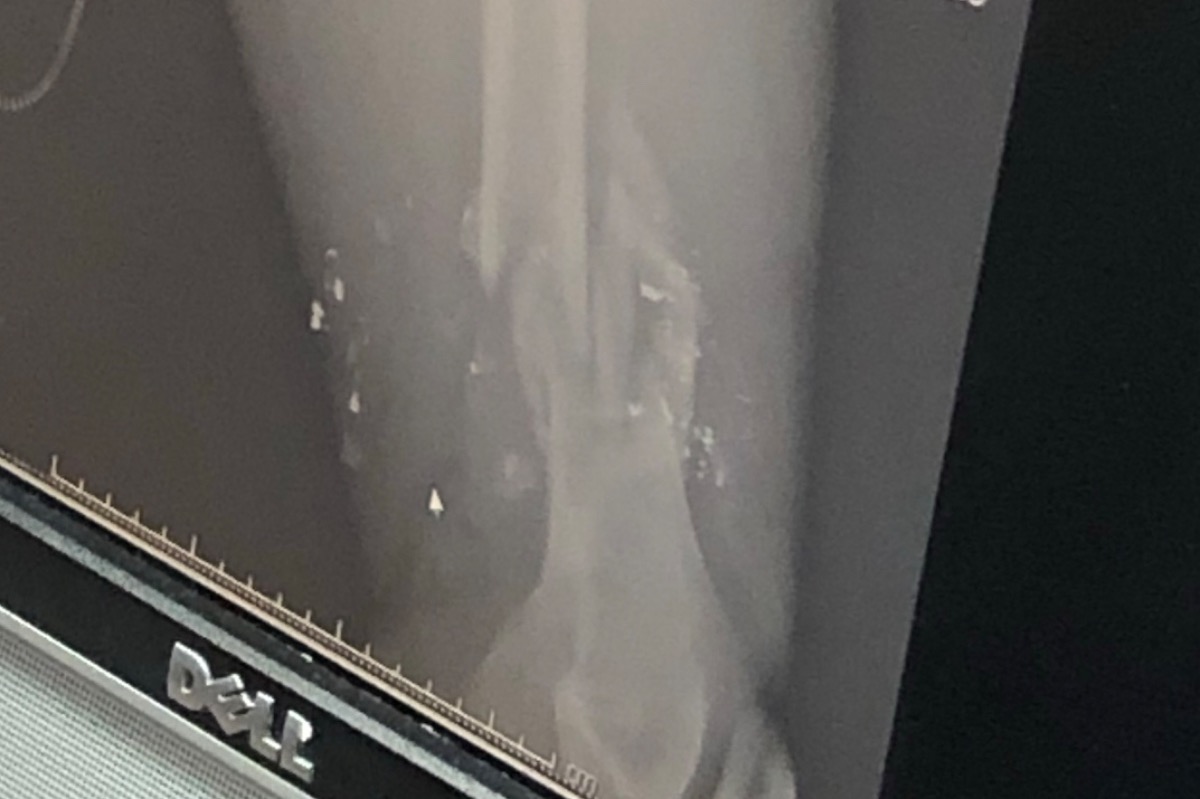

Many of you heard that my brother Anatoly was shot while being robbed last week.. We are thankful to our Lord that he is with us and ask everyone to keep him in your prayers, that he will be restored and be able to be there for his wife and 3 boys.. He has had 4 surgeries and is at risk of losing his left leg... On Thursday Nov. 7th, 2019; Anatoly was driving his tractor trailer home from Chicago and stopped in Indianapolis for a break and meal.. He was robbed at a Subway in broad daylight and the suspect shot him point blank above his left knee, shattering his femur and artery... Upon getting transported and prepped for surgery, his lower leg had been without proper blood circulation for over 4 hours. The initial surgery lasted close to 5 hours and required a vein transplant, artery bypass, and rods to replace shattered missing bone. Once the blood flow was restored, his lower leg swelled rapidly and had to be opened to relieve pressure. They are actively monitoring his CK(dead tissue enzyme count) to ensure that the leg heals properly. He has had 3 additional surgeries in the past week to remove dead or dying Muscle tissue.. the next couple days are critical and the doctors are trying their best to save the leg.. Olga has been by his side and their three boys are being cared for by family... This is a totally unexpected tragic event that as usual, came at a bad time. Anatoly is the main breadwinner and they are in the middle of building a house. Hospital expenses and travel are going to be substantial.. please keep them in your prayers and if it’s on your heart to support them in this tough time please consider it and be blessed.. I will try to update as he progresses.. a big surgey is scheduled for tomorrow..